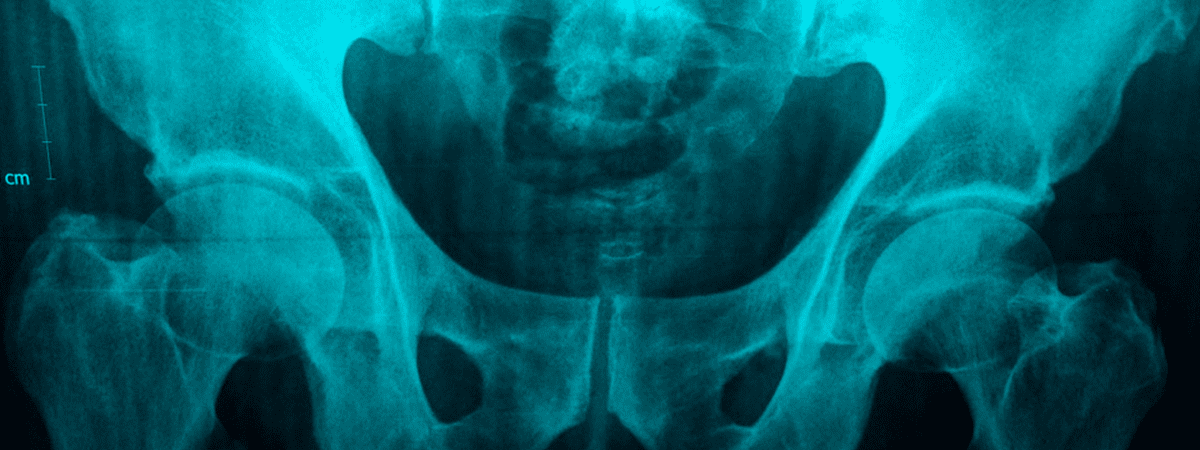

Con el objetivo de estudiar las características de los pacientes ancianos con fractura de cadera (FC) en España, en 2017 se puso en marcha el Registro Nacional de Fracturas de Cadera (RNFC), en el que actualmente participan 52 hospitales repartidos por todo el territorio. Entre las funciones del registro también se encuentran el análisis de la variabilidad en el manejo clínico de este tipo de fracturas por fragilidad y la mejora de la calidad asistencial.